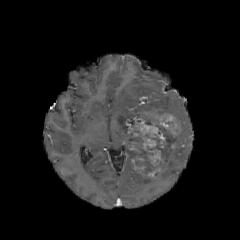

We first introduce a method for connecting the output of a CNN to an ACM, yielding a model for the precise delineation of lesions, to which we refer as Deep Active Lesion Segmentation (DALS) (Figure 4). We then go further to introduce a truly unified framework (Figure 5) that bridges the gap between ACMs and CNNs by leveraging a novel, automatically differentiable level-set ACM with trainable parameters that allows for back-propagation of gradients and can be end-to-end trained along with a backbone CNN from scratch, without any CNN pre-training. The ACM is initialized directly by the CNN and utilizes an energy functional that is locally-tunable by the backbone CNN, through 2D feature maps. Thus, our work overcomes the big hurdle of fully automating the powerful ACM approach to image segmentation. We have applied our proposed framework to the task of building segmentation in aerial images (Figure 6).

Deep Active Lesion Segmentation

[45]: Lesion segmentation is an important problem in computer-assisted diagnosis that remains challenging due to the prevalence of low contrast, irregular boundaries that are unamenable to shape priors. We introduce Deep Active Lesion Segmentation (DALS), a fully automated segmentation framework that leverages the powerful nonlinear feature extraction abilities of FCNs and the precise boundary delineation abilities of ACMs. Our DALS framework benefits from an improved level-set ACM formulation with a per-pixel-parameterized energy functional and a novel multiscale encoder-decoder CNN that learns an initialization probability map along with parameter maps for the ACM. We evaluate our lesion segmentation model on a new Multiorgan Lesion Segmentation (MLS) dataset that contains images of various organs, including brain, liver, and lung, across different imaging modalities—MR and CT. Our results demonstrate favorable performance compared to competing methods, especially for small training datasets. -